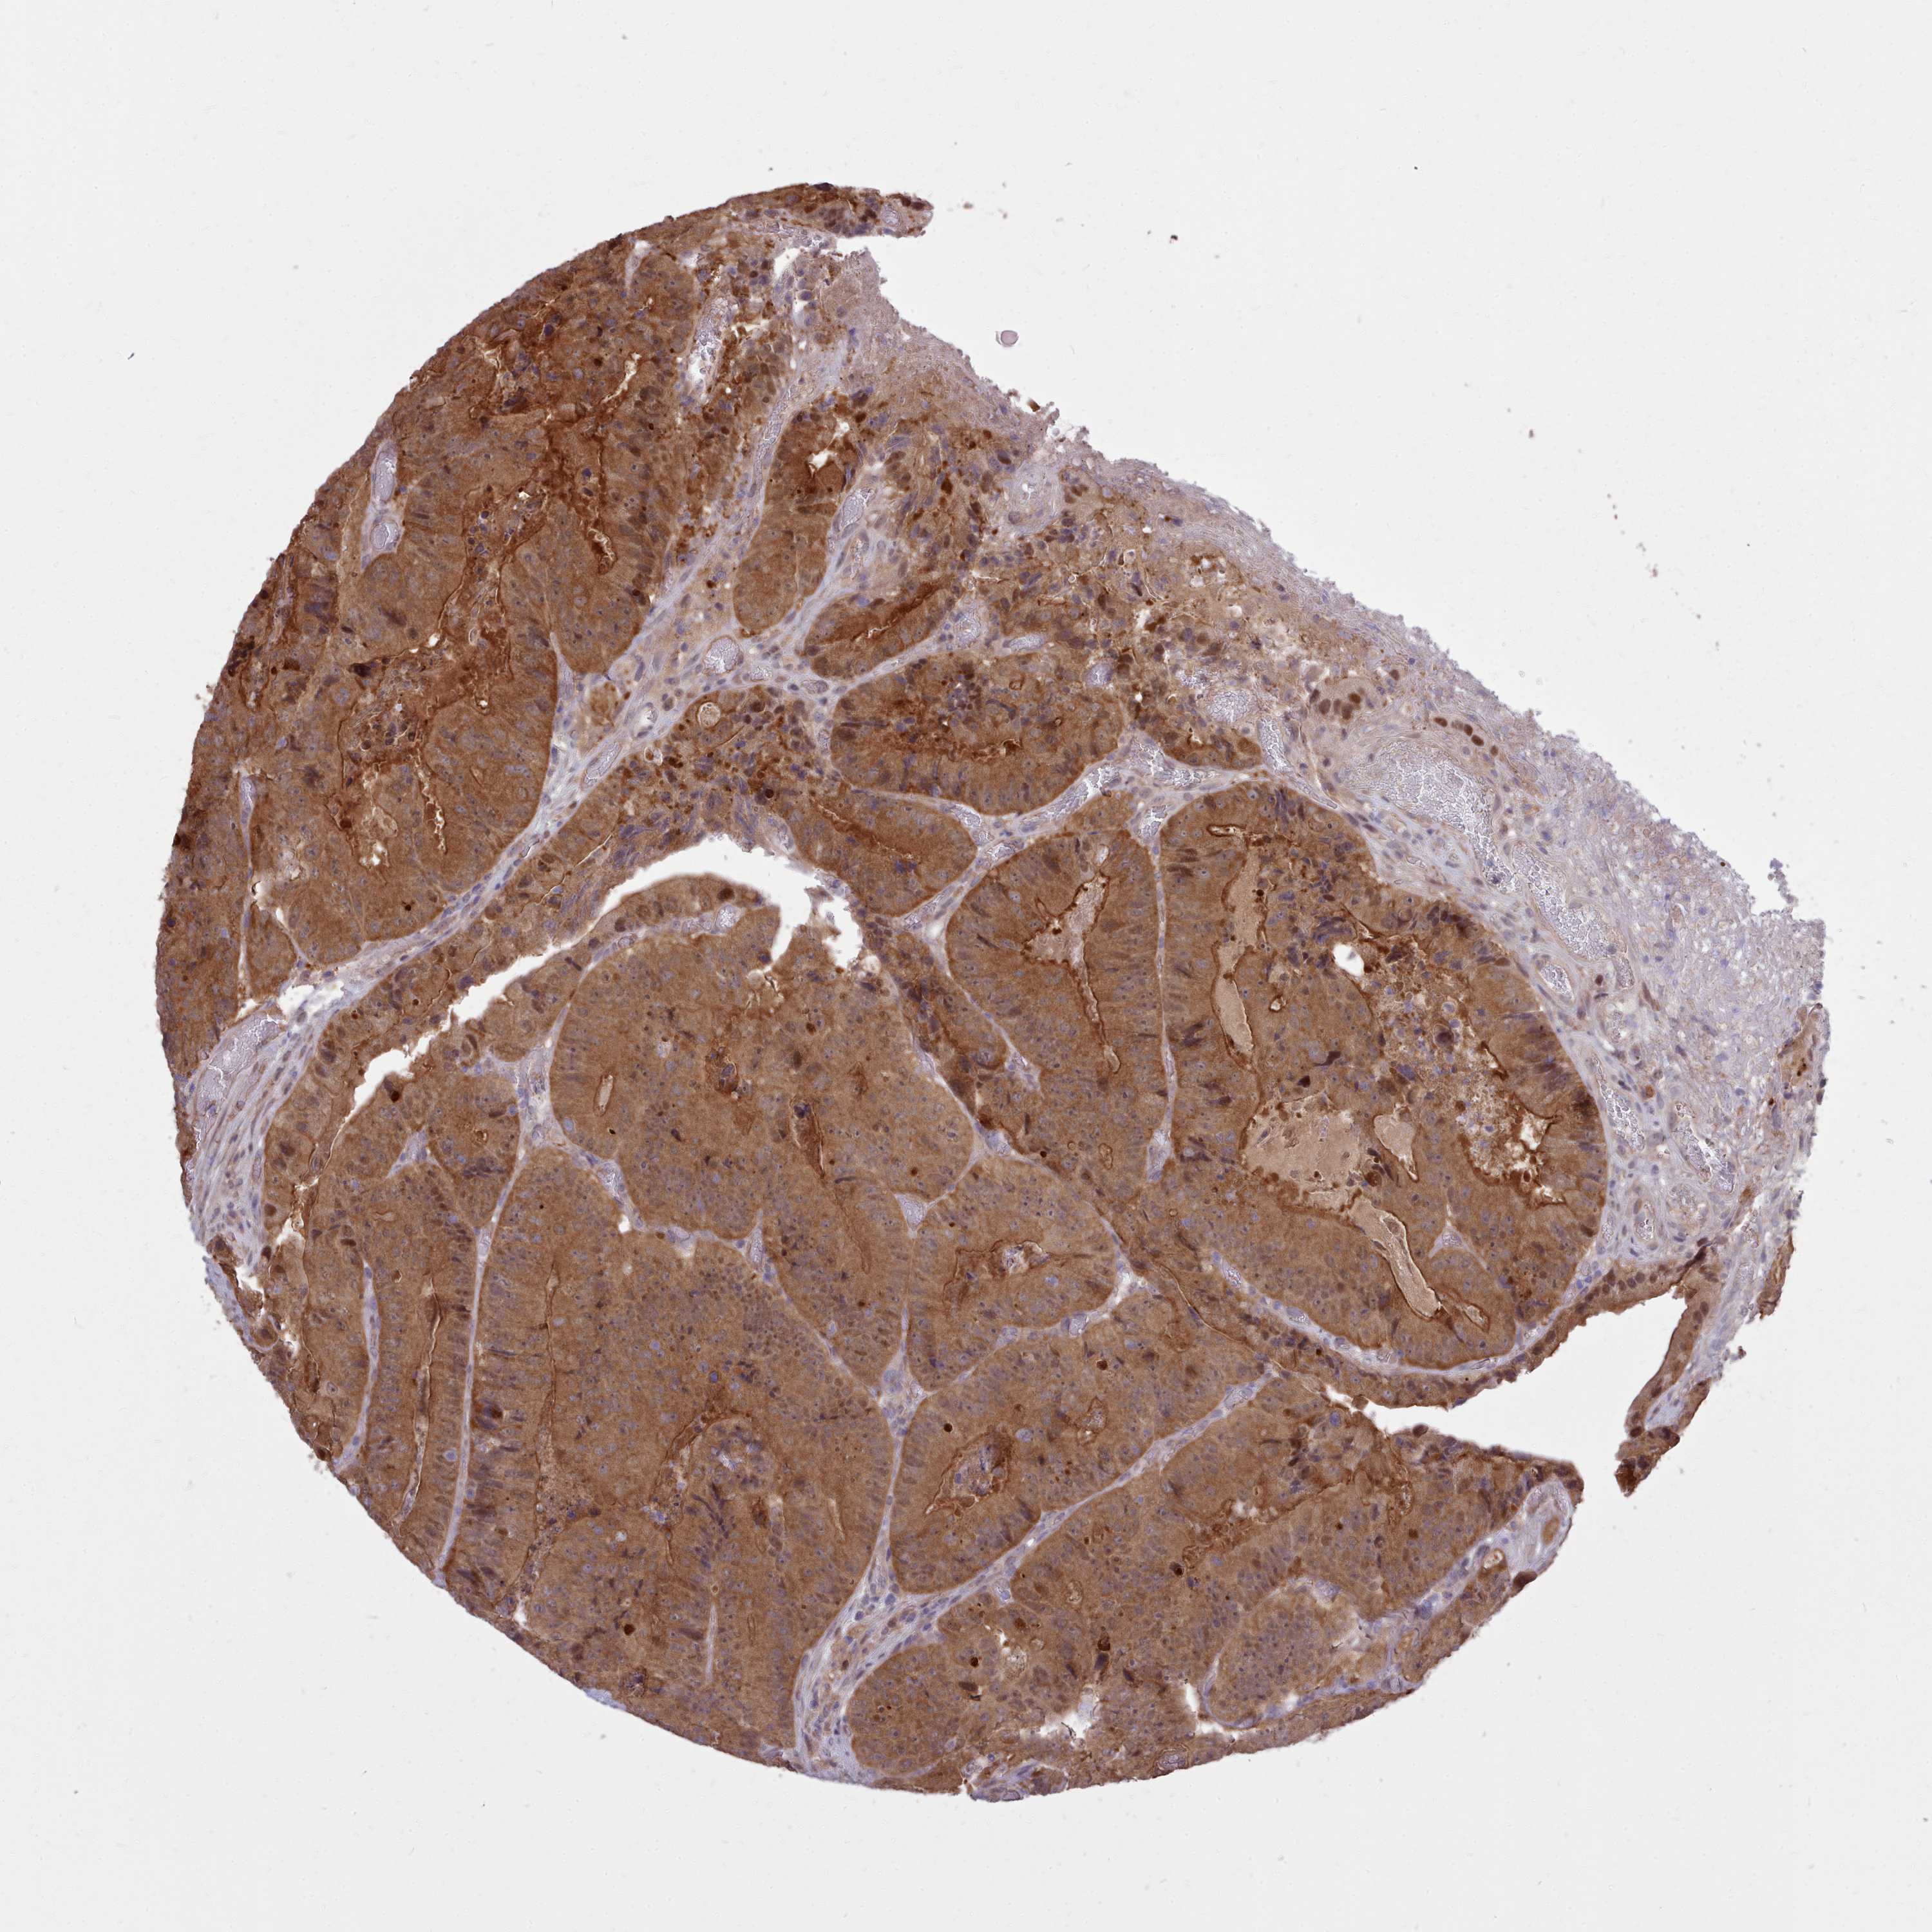

AHCY

CANCER COLORECTAL CANCER Show tissue menu

Colorectal cancer

Human cancer

Colon adenocarcinoma